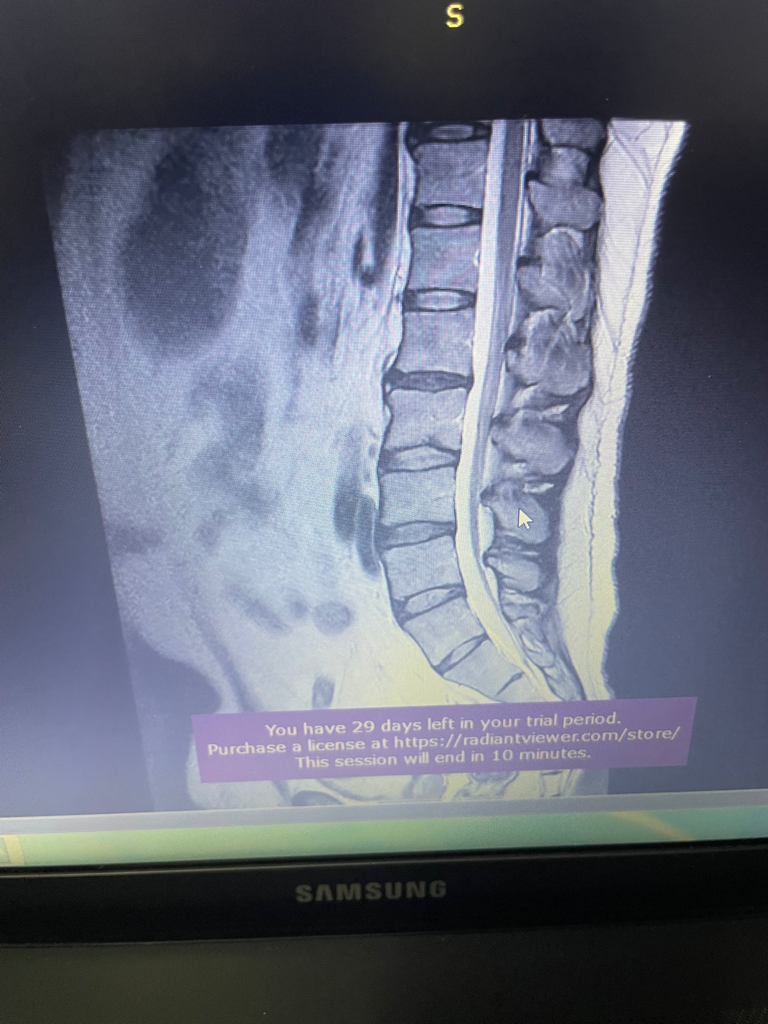

허리디스크 1.2번 3.4번 경미한디스크

꼬리뼈 엉치양쪽통증 어벅지 양쪽 무릎 양쪽통증 무릎서있거나 누워을때 심하고 걸을때도 조금식 심해짐니다 앉을때 자전거 탈때는 무릎통증이 없어요 어리때문에 무릎통증이 오는걸 까요

허리디스크로 인해 통증이 발생했을 수 있습니다.